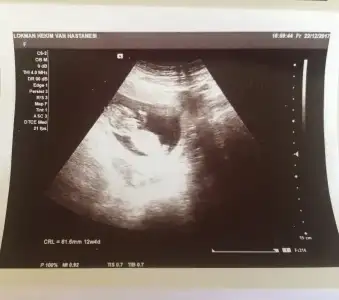

ben baska arkadasa ultrason goruntusunden genital nub tahmini yapmistim tutmus. Ama bir turlu kendiminkini bilemiyorum ya nasil bir kisiligim var anlamadim gitti :KK45:

IMG-20180103-WA0001.webp bu ne sence 10 haftalik tam